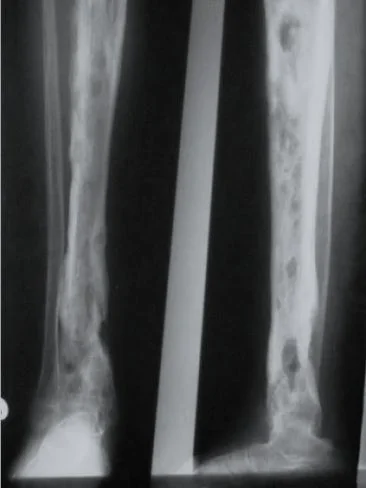

The initial radiographs are normal as bone changes are not visible until 10–14 days after the onset of infection.

X-ray is the recommended initial imaging modality because it is inexpensive and can rule out differential diagnoses.

The earliest signs on plain radiographs are soft tissue swelling and bone destruction in the metaphysis, with a Periosteal reaction.

(A) Â An initial films reveals no abnormality

(B) A film taken 3 weeks later shows some destruction of the upper end of the tibia and an extensive periosteal reaction along the tibia, particularly the medial side (arrow).

(C) Bony sequestrum X-ray leg (left; AP view) of a child A fragment of bone has separated from adjacent bone and is surrounded by a lucent rim. chronic osteomyelitis.Â